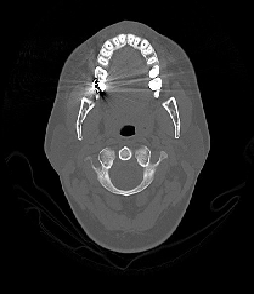

No departamento de imagens do HC foram adquiridas 3 imagens de tomografia computadorizada no formato DICOM que mostra a parte inferior dos dentes de uma pessoa. Foram gerados 3 segmentos (Fatias) dessa imagem no qual o terceiro segmento apresentou um nível alto de ruído, gerando um pequena distorção nos dados da imagem. Essa distorção foi causada por um material metálico que é utilizado na obturação dos dentes. Essa imagem foi escolhida por causa do tamanho e da complexidade que o ruído provoca.

Figura 1 – Os 3 segmentos adquiridos no laboratório de imagens.